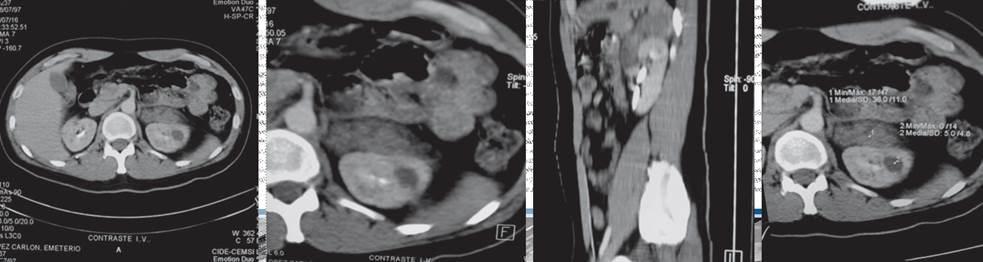

Paciente masculino de 36 años de edad, sin antecedentes de importancia para el padecimiento actual, con una sensación intermitente de pesantez en la fosa renal izquierda y el flanco ipsilateral, de cuatro meses de evolución, sin síntomas agregados. Después de su recepción en el servicio médico se efectuó un ultrasonido abdominal que reportó una masa adyacente en el riñón izquierdo, en su porción superior, de aproximadamente 5 x 4 cm, hipoecoica, sin calcificaciones en su interior. La tomografía computada abdominopélvica simple y contrastada evidenció una neoplasia suprarrenal izquierda, de aproximadamente 8 x 5 cm, con 22 Unidades Hounsfield en promedio, sin reforzamiento significativo después de la aplicación del medio de contraste (Figura 1). Con estos hallazgos se envió al servicio de Urología del Hospital General de Culiacán Dr. Bernardo J. Gastélum.